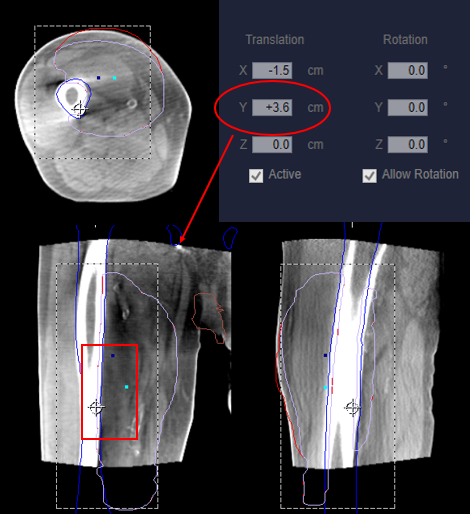

- Longitudinal offsets: If the treatment area is centered within a long field, for example the femur, a longitudinal shift may be helpful to visualize anatomy and confirm correct positioning in the superior/inferior directions – see Figure 4.

- Figure 4; long. offset © The University of Iowa Radiation Therapy Program is licensed under a CC BY (Attribution) license